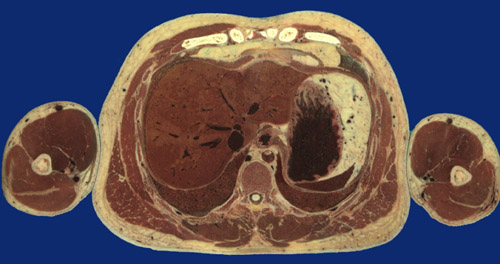

Identify the following regions in the image above: Latissimus dorsi - Serratus anterior - External oblique - Rectus abdominus - Sacrospinalis - Trapezius - Xyphoid process - Liver - Stomach - Greater omentum - Spleen - Left lower lobe - Right lower lobe - Esophagus - Descending aorta - Inferior vena cava - Vertebral body - Spinal cord -